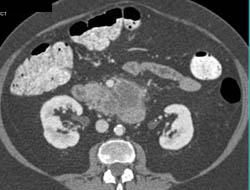

Islet Cell Carcinoma With Vascular Liver Metastases